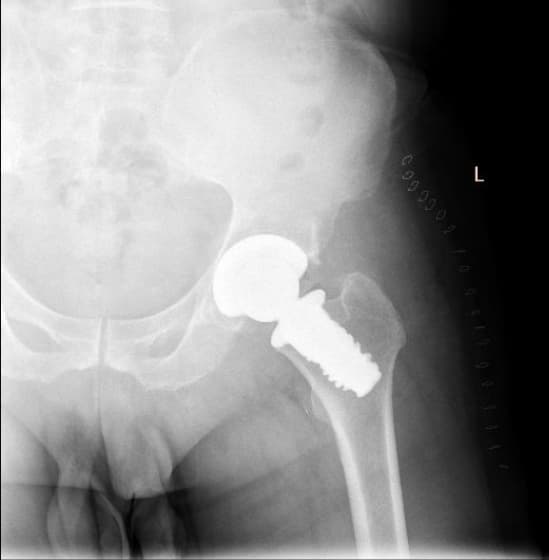

Түнхний үеийг хамарсан хавдарын үед хиймэл үе суулгах мэс заслын өмнөх болон дараах зураг

Түнхний үе бүтэн солих мэс засал (THA) image7Түнхний үе бүтэн солих мэс засал (THA) image8Түнхний үе бүтэн солих мэс засал (THA) image9